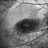

- plaquenil toxicity, bull's eye maculopathy, bull's eye atrophy, hydroxychloroquine toxicity

- Optical coherence tomography system

- Fundus autofluorescence image of the right eye in a highly myopic Caucasian patient who was screened for plaquenil toxicity elsewhere for 15 years. Medicine was stopped 3 years ago. She presented to us with deteriorationg central vision and scotoma for the past 3 years. FAF demonstrtaes classic symmetric bull's eye pattern of hypoautofluorescence in parafoveal area both eyes with some extension to the arcades, which is the result of severe plaquenil toxicity. Notice the hyperAF area surrounding the bull'e eye which is demonstarting stressed RPE cells filled with Lipofuscin. This area will likely turn to a larger hypoAF later. It is critical to diagnose it early to prevent the ongoing damage and loss of RPE and photoreceptors from the long term deposited medicine in RPE cells.